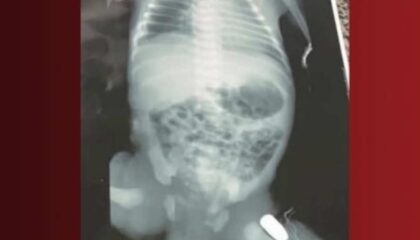

BrasilBebê é baleado na barriga da mãe e sobrevive após cirurgia de emergênciaA mãe da criança foi baleada na barriga e teve que fazer uma cesariana de urgência; o caso aconteceu em Imperatriz no interior do…